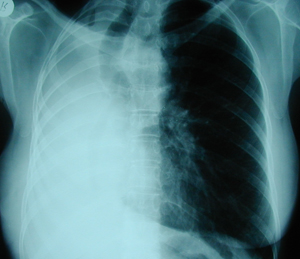

Εικόνα 4

Οπισθιοπροσθία ακτινογραφία θώρακος πολλά χρόνια μετά από δεξιά πνευμονεκτομή. Πλήρης κατάληψη του χώρου της πνευμονεκτομής από υγρό, υπερέκπτυξη του αριστερού πνεύμονος και έλξη του μεσοθωρακίου προς την χειρουργηθείσα πλευρά.